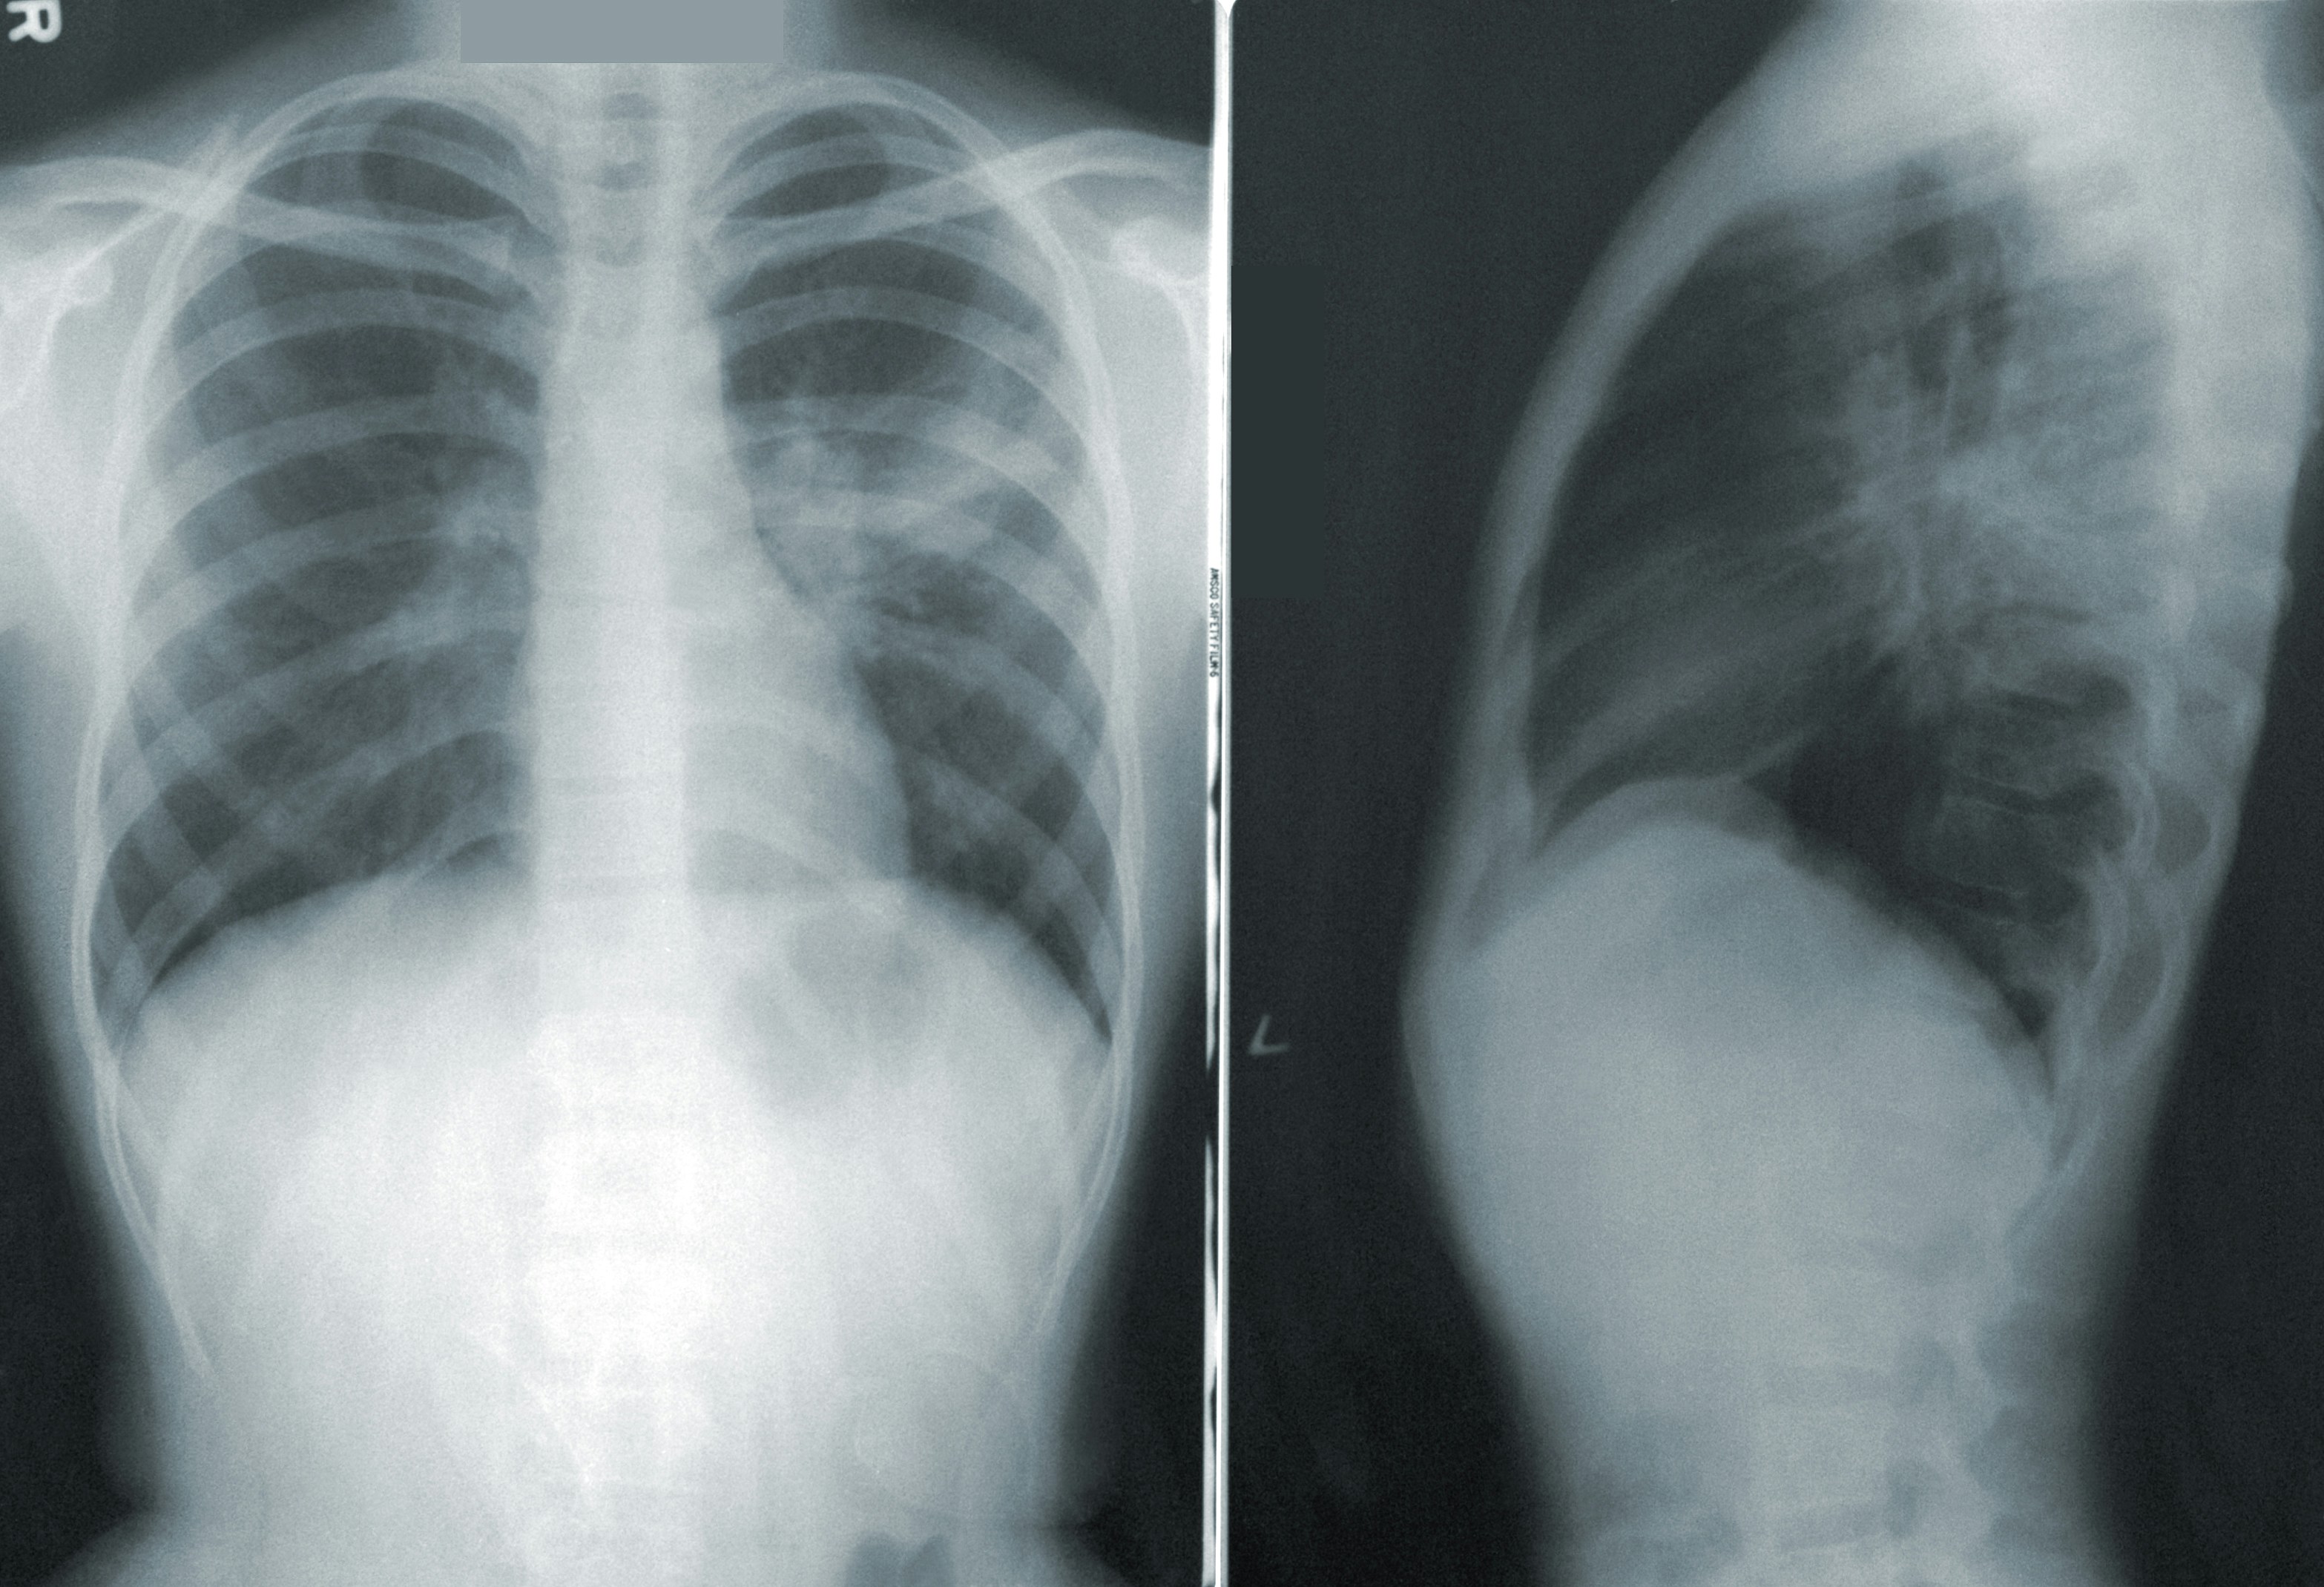

- 흉부 X-ray

흉부 X-ray: 폐의 염증 정도와 폐렴의 위치를 확인하기 위해 사용됩니다. 마이코플라즈마 폐렴의 경우, 폐렴 패턴이 균일하지 않고 퍼져 있는 모양을 보이는 경향이 있습니다.

- 심각한 폐렴 소견

심각한 폐렴 소견: 흉부 X-ray에서 폐렴의 정도가 심각하게 나타나거나, 흉수가 고여 호흡 곤란이 있는 경우 입원이 필요합니다.